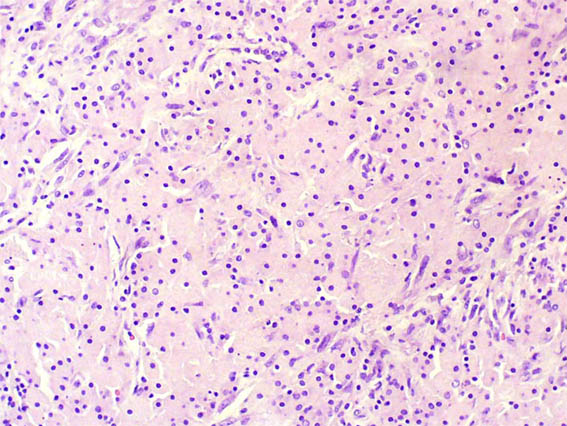

The patient is a 67-year-old woman with renal mass that completely replaced the left kidney. No lithiasis.

Nephrectomy was done.

Figure 4. H&E, X400.